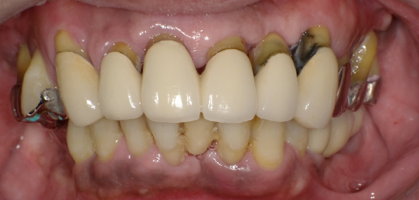

前歯に連結固定した差し歯が入っています。おそらく奥歯がなりなり、噛めなくなるので、前歯でしっかり噛めるように連結固定したのだと思いますが・・

治療前の写真です。前歯がぐらぐらになっています

奥歯がなくなり、前歯ばかりで噛んでいるとフレアーアウトといって前歯がどんどん前に傾いて出てきます。

術後の写真です。フレアーアウトした分、歯を引っ込めてかみ合わせも若干高くしています。

術前の口元と別人になっているのが分かると思います。

オールオンフォーの良いところはこのように好きなように歯を並べることができることです。